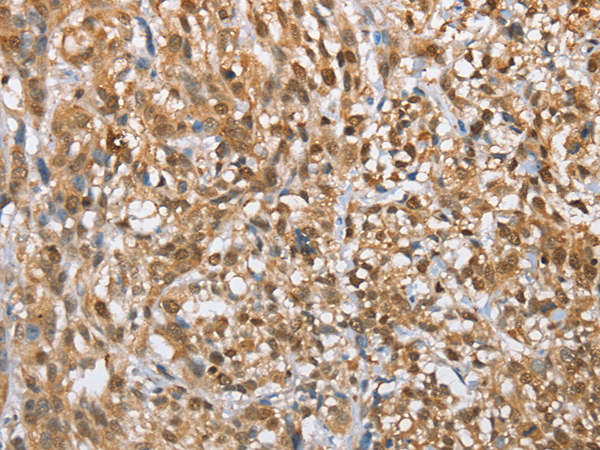

分类: 科研抗体货号: P07473别名: EBN; BFNC; EBN1; NACHR; NACRA4; NACHRA4应用: WB,IHC反应种属: Human